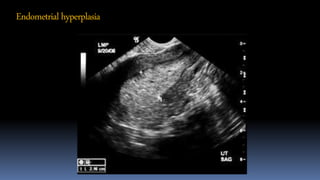

Endometrialhyperplasia

• Endometrial thickness - > 5mm

• Hyper or mixed echoic endometrium.

• Irregular interrupted endo-myometrial interface

• Multiple, densely packed, large, irregular branching

vessels.

• High color scoring.

• SIS showing irregular surface